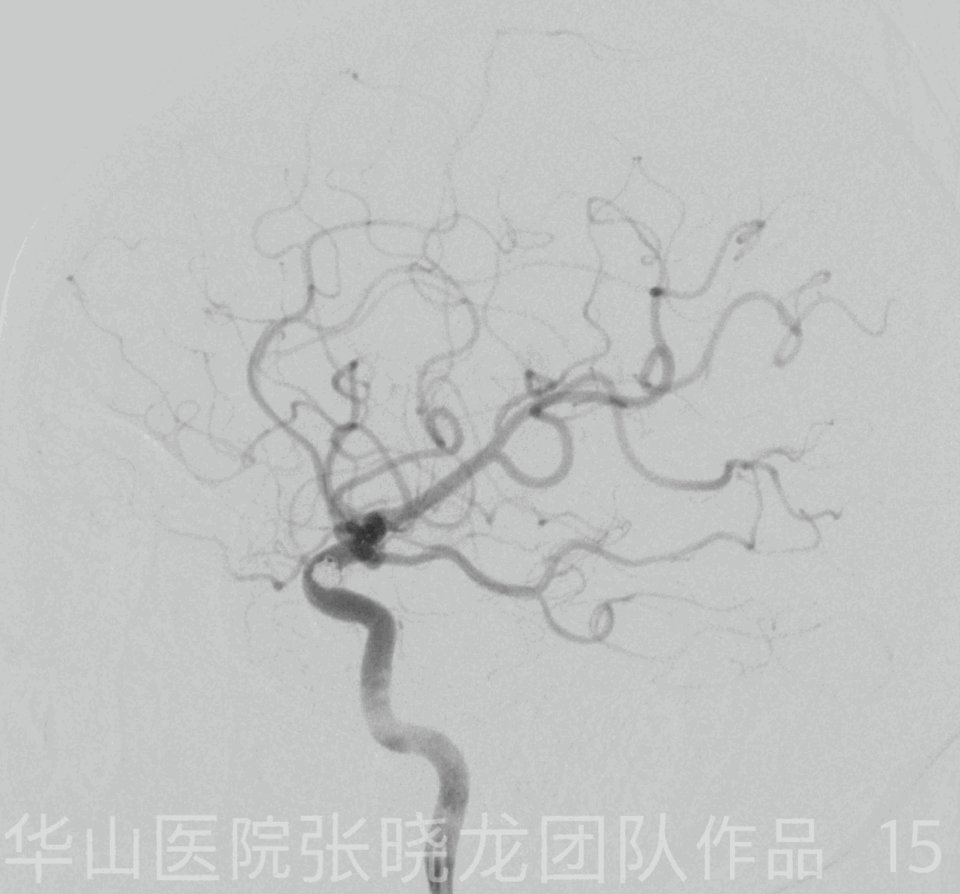

Figure 15 GIF. Post operative rotational angiography shows densely packing of the aneurysm with the parent artery patent. Tirofiban (Xinweining) 10ml was administrated. 图 15. 术后旋转血管造影显示动脉瘤致密栓塞,载瘤动脉通畅。应用替罗非班(欣维宁)10ml。

Figure 17. The three working projections have different purposes:

图 17. 三个工作角度有不同的目的:

角度I:显示动脉瘤颈和相邻的载瘤动脉。

角度II:显示子瘤以便于栓塞并显示意外穿破的危险点。

角度III:显示流入道以便于致密栓塞,降低复发率。

5.The three working projections have different purposes:

I: to show the aneurysm neck and adjacent parent artery

II: to reveal the daughter sac for embolization and in case of accidental puncturing.

III: to show the inflow tract for densely packing and decrease the recurrence rate.